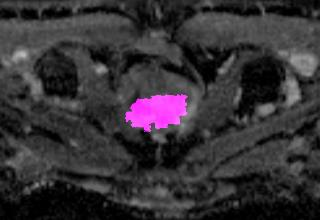

Weakly Supervised Semantic Segmentation (WSSS) relying only on image-level supervision is a promising approach to deal with the need for Segmentation networks, especially for generating a large number of pixel-wise masks in a given dataset. However, most state-of-the-art image-level WSSS techniques lack an understanding of the geometric features embedded in the images since the network cannot derive any object boundary information from just image-level labels. We define a boundary here as the line separating an object and its background, or two different objects. To address this drawback, we are proposing our novel ReFit framework, which deploys state-of-the-art class activation maps combined with various post-processing techniques in order to achieve fine-grained higher-accuracy segmentation masks. To achieve this, we investigate a state-of-the-art unsupervised segmentation network that can be used to construct a boundary map, which enables ReFit to predict object locations with sharper boundaries. By applying our method to WSSS predictions, we achieved up to 10% improvement over the current state-of-the-art WSSS methods for medical imaging. The framework is open-source, to ensure that our results are reproducible, and accessible online at https://github.com/bharathprabakaran/ReFit.